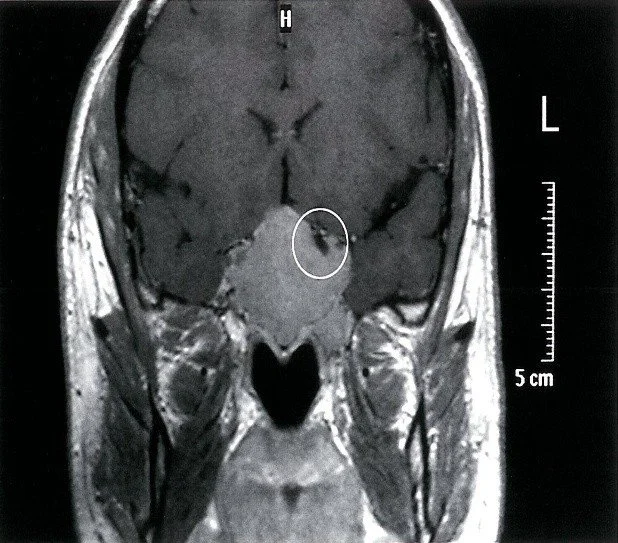

Diagnosis

• Low pituitary hormone levels

• MRI showing pituitary atrophy